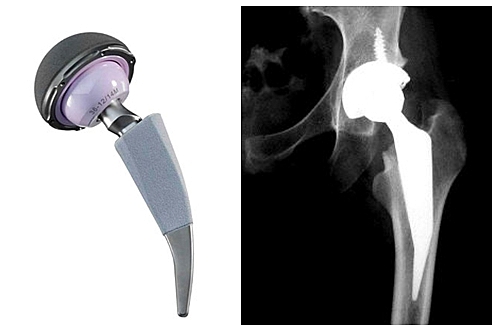

ARTROPLASTIA ACTUAL

Se continua investigando en la actualidad la mejora de los reemplazos, así mismo en la ultima actualización de las protesis, se implementan nuevos elementos como cromo, cobalto,ceramicos y el anteriormente mencionado cemento oseo para la fijacion, asi mismo un vastago mas largo y mejor adaptable

• APARICION DE LA HIDROXIAPATITA

APARICION DE LA HIDROXIAPATITA

Este nuevo recubrimiento aplicado en la actualidad busca mejorar y disminuir las complicaciones que se pueden presentar y mejorar la vida útil de la prótesis, disminuir al máximo todos los factores que llevan al desgaste o aflojamiento de esta